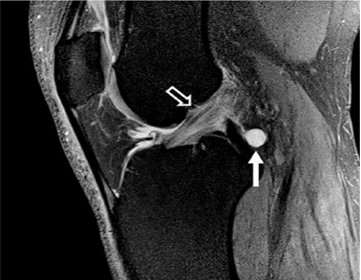

Hình 5. Vết rách ngang sụn với mảnh di lệch. Hình ảnh pd xóa mỡ với vết rách sụn chêm giữa và mảnh di lệch (mũi tên) nằm giữa dây chằng chéo giữa và mâm chày giữa.

Hình 6. Nốt sần sụn chêm. Hình ảnh pd sagittal cho thấy một nốt sần hình sụn (mũi tên) ở vùng của rễ sụn trung gian sừng sau.